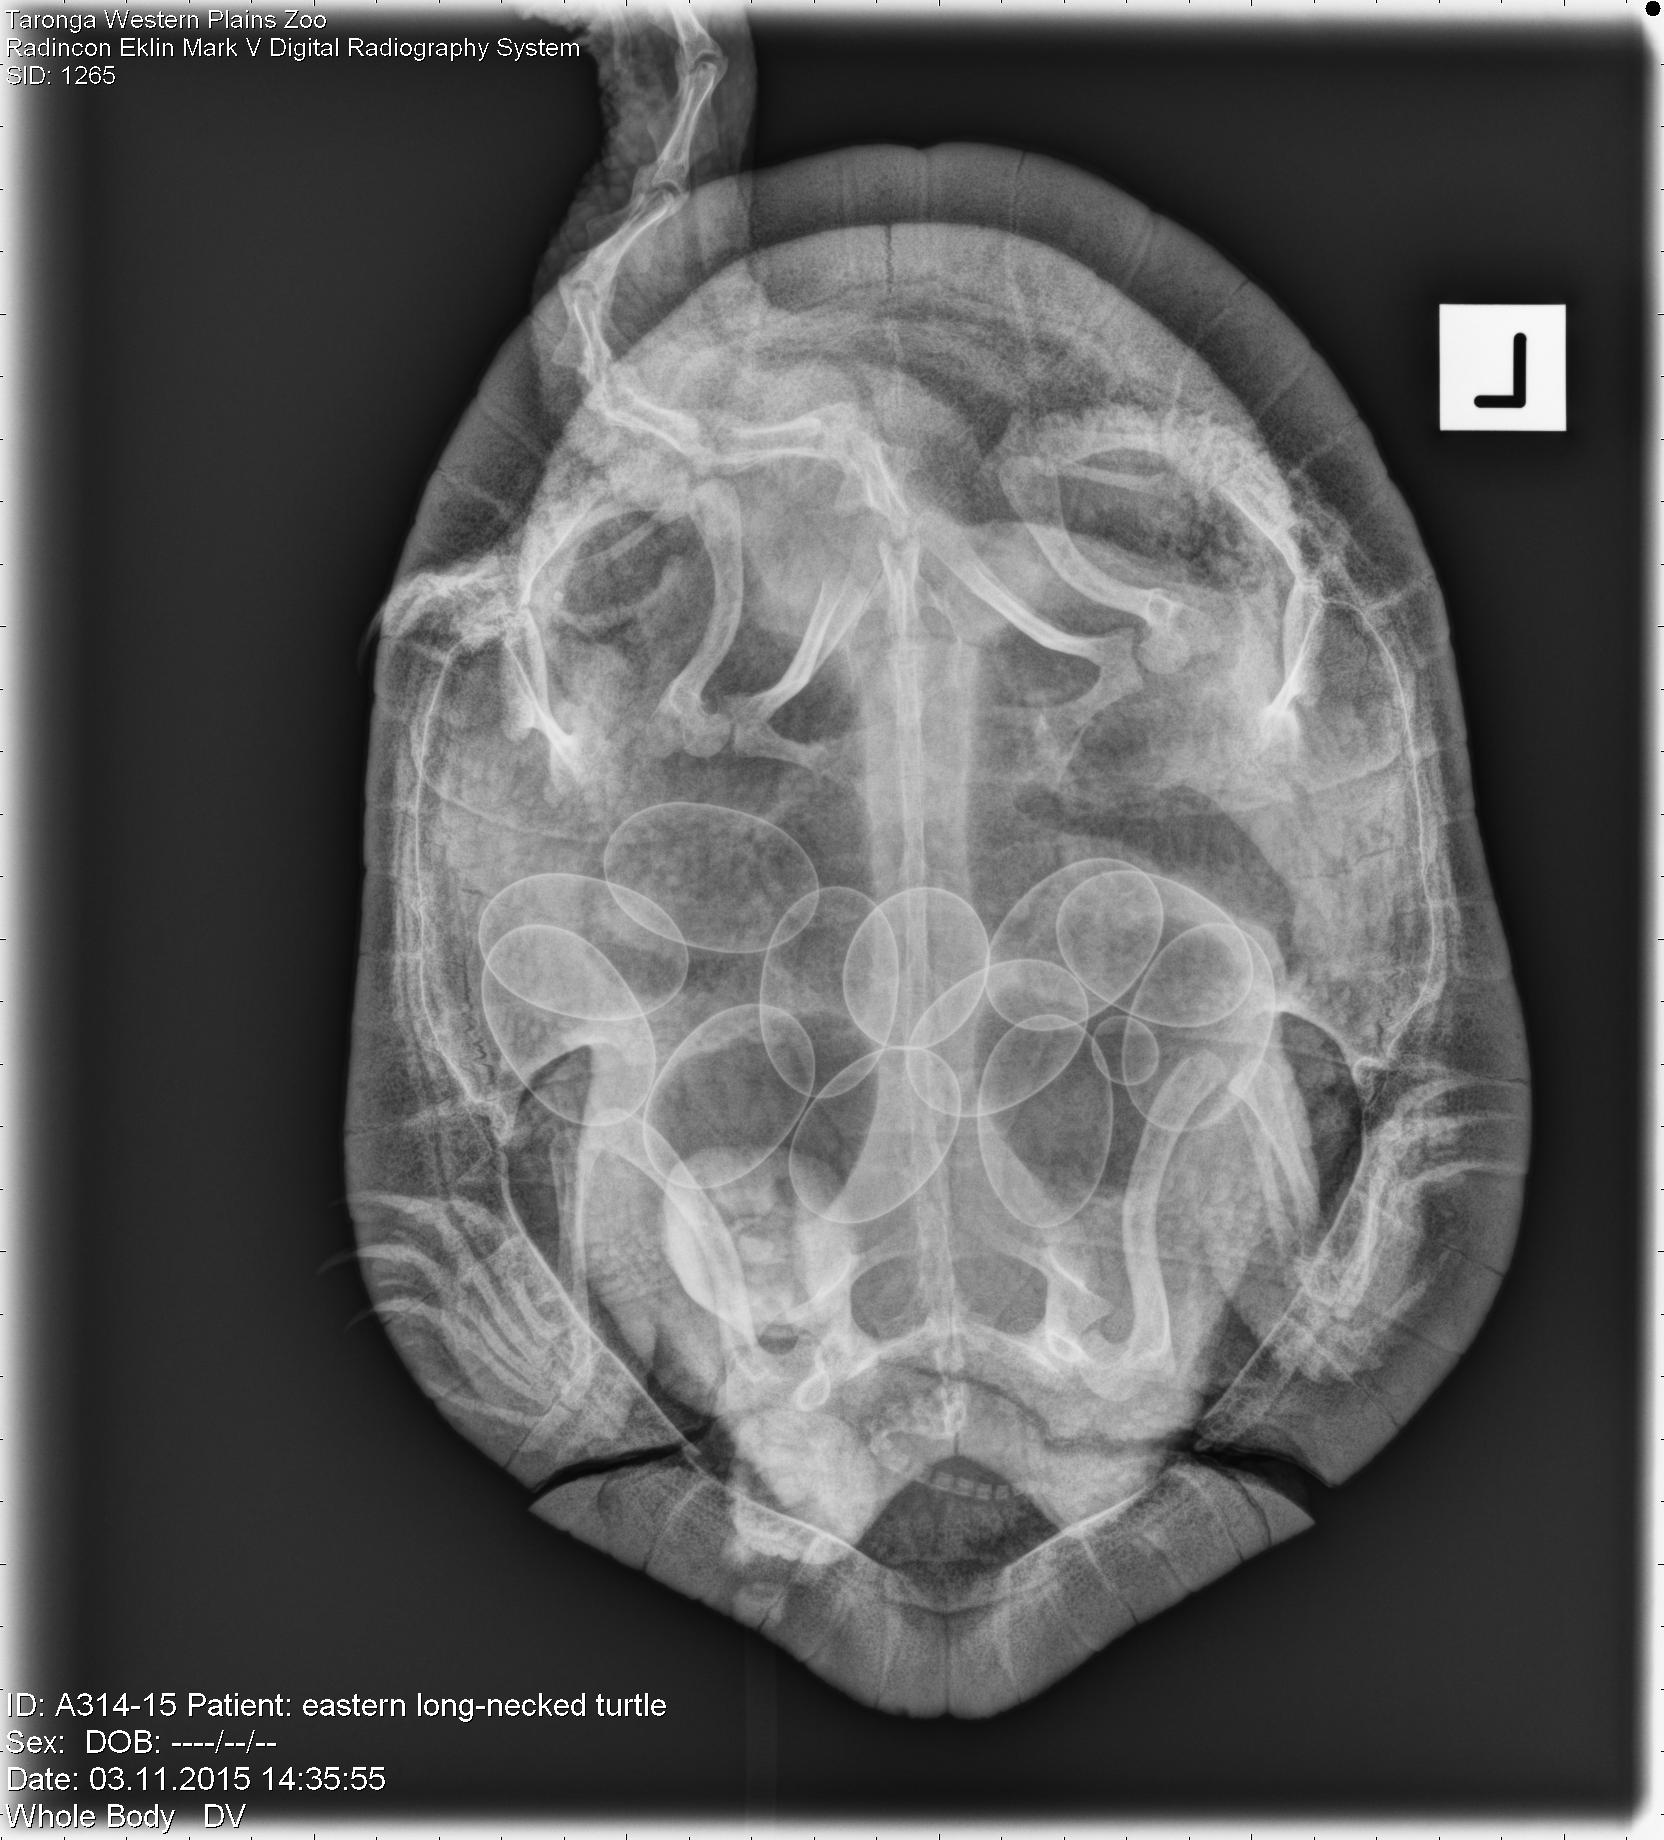

X-rays were taken throughout the turtle’s hospitalisation period to ensure the fracture site was healing correctly. When the vets took the final x-ray before release they noticed the turtle was gravid ie. she had shelled eggs in her reproductive tract. Female turtles can develop eggs even if they have not mated and animals that have mated in the past may retain sperm for a prolonged period and develop fertilised eggs later.

After approximately three months at the Wildlife Hospital the veterinary team were satisfied that the fracture site had healed and her general health was good. The brackets were removed and she was released into a pond within the zoo grounds to allow her to find a suitable place to lay her eggs.